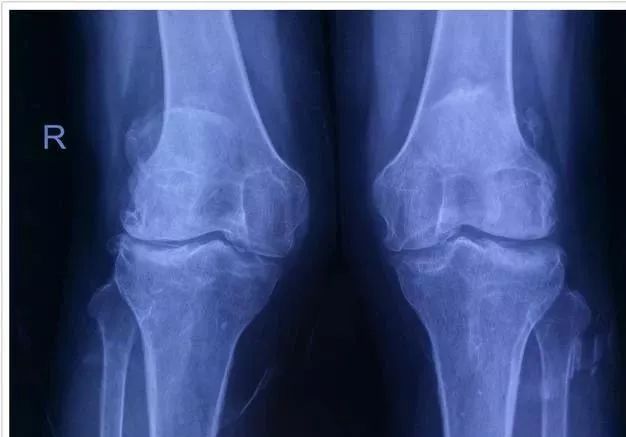

骨性关节炎(osteoarthritis,OA)俗称"骨质增生"或"骨刺",是一种以关节软骨的变性、破坏及骨质增生为特征的退行性病变, 又称骨关节病、退行性关节炎、老年性关节炎、肥大性关节炎等。

OA在60岁以上的人群中患病率可达50%,75岁以上的人群中则达80%,致残率可高达53%。临床表现为缓慢发展的关节疼痛、压痛、僵硬、关节肿胀、活动受限和关节畸形等,是老年人中最常见的活动障碍原因之一。OA好发于膝关节,称为膝骨关节炎(KOA),对人类健康的影响程度以及所造成的医疗费用不断增加。